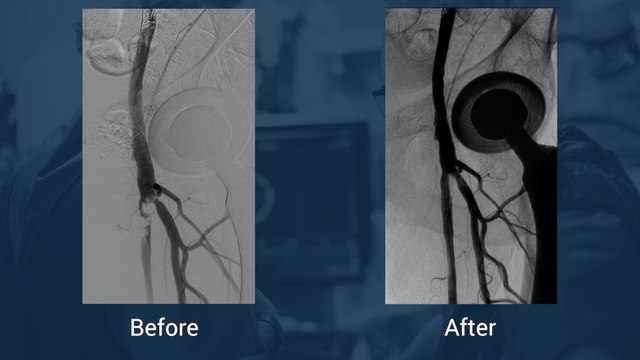

Renal Stenting, Incathlab

Uploaded: July 18, 2013 Views: 177